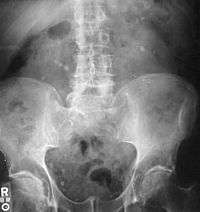

Otherwise a noncontrast helical CT scan with 5 millimeters (0.2 in) sections is the diagnostic modality of choice in the radiographic evaluation of suspected nephrolithiasis.[12][42][45][46][3] All stones are detectable on CT scans except very rare stones composed of certain drug residues in the urine,[47] such as from indinavir. Calcium-containing stones are relatively radiodense, and they can often be detected by a traditional radiograph of the abdomen that includes the kidneys, ureters, and bladder (KUB film).[47] Some 60% of all renal stones are radiopaque.[45][48] In general, calcium phosphate stones have the greatest density, followed by calcium oxalate and magnesium ammonium phosphate stones. Cystine calculi are only faintly radiodense, while uric acid stones are usually entirely radiolucent.[49]

Where a CT scan is unavailable, an intravenous pyelogram may be performed to help confirm the diagnosis of urolithiasis. This involves intravenous injection of a contrast agent followed by a KUB film. Uroliths present in the kidneys, ureters or bladder may be better defined by the use of this contrast agent. Stones can also be detected by a retrograde pyelogram, where a similar contrast agent is injected directly into the distal ostium of the ureter (where the ureter terminates as it enters the bladder).[45]